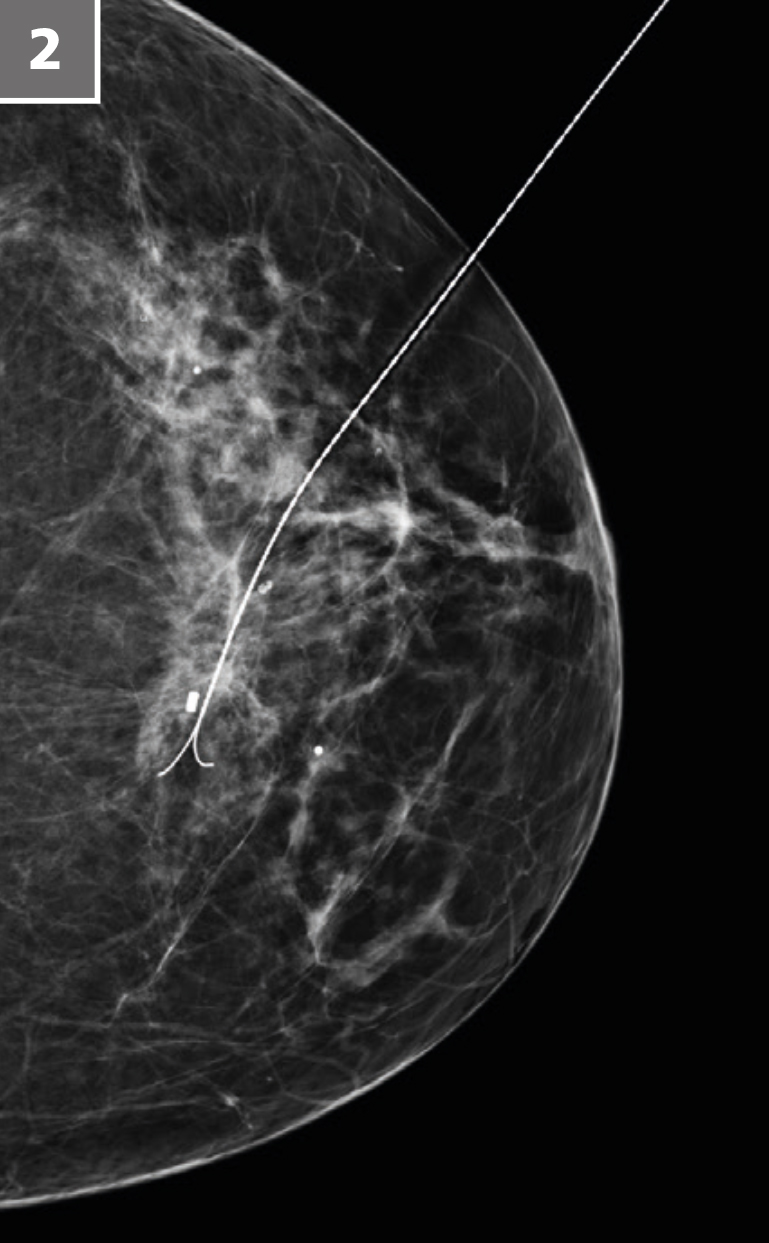

2019 war ein »Nichtscreeningjahr« für unsere Region, trotzdem haben wir die zweithöchste Patientenzahl für Mammografien seit Bestehen des Südharz Klinikums gehabt. Mit unserer sehr modernen Technik können wir nicht nur reguläre Mammografien anbieten, sondern auch Kontrastmitteluntersuchungen in der Mammografie durchführen, was für Patienten mit Kontraindikationen für das Mamma-MRT hilfreich ist. Außerdem haben wir die Möglichkeit, Schichtaufnahmen (Tomosynthesen) anzufertigen und auch anhand der Tomosynthesebilder eine Biopsie durchzuführen, was in Thüringen nur sehr wenige Zentren technologisch anbieten. Im Gegensatz zum Screening findet bei uns, wenn erforderlich, auch direkt im Anschluss an die Mammografie der Brustultraschall statt (es sei denn, dieser wird vom überweisenden Gynäkologen durchgeführt). Wie im Screening auch erfolgt bei uns eine geblindete Doppelbefundung von zwei erfahrenen Fachärzten, die die jeweilige Bewertung der Bilddaten des anderen Kollegen nicht kennen. Mit den verschiedenen Möglichkeiten der Biopsie, der Bildgebung und der persönlichen Bindung vieler Patientinnen an unsere Abteilung verbunden ist ein kontinuierlicher Anstieg der Untersuchungen, was sich auch in den bereitgestellten deutlich erweiterten Kapazitäten bei Terminen zeigt. Zielstellung dabei ist, dass es keine emotional belastenden längeren Wartezeiten für die Brustbildgebung gibt. Die stetig steigenden Patientenzahlen geben uns bei dieser Strategie recht. Das hat auch Vorteile für die Ausbildung junger Assistenzärzte, weil in vielen radiologischen Abteilungen und Kliniken gar keine Mammografien mehr durchgeführt werden. Bei uns steigt die Bedeutung der Mammografie beständig.

Stereotaktische Drahtmarkierungen50